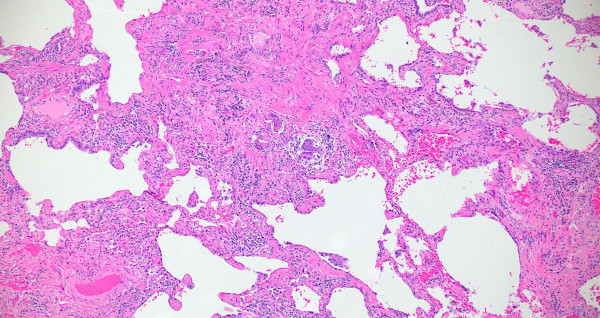

Compute tomography (CT) scan of the chest showed subpleural and peribronchial fibrosis with air-trapping on expiratory phase. The findings were read as likely “non-IPF pattern.” A serum antibody panel for hypersensitivity pneumonitis was positive for antibodies to Aspergillus flavus. Histologic sections of her lung biopsy demonstrated airways with peribronchiolar fibrosis with extensive metaplastic changes (Figure 1). Intra-alveolar giant cells and histiocytes with cholesterol clefts were seen (Figures 2-3). There were areas of interstitial inflammation and fibrosis resembling a cellular non-specific interstitial pneumonia (NSIP) pattern of injury (Figure 4). Also seen were extensive peribronchiolar metaplasia, microscopic “honeycombing”, interstitial giant cells, and poorly-formed granulomata (Figures 5-7).